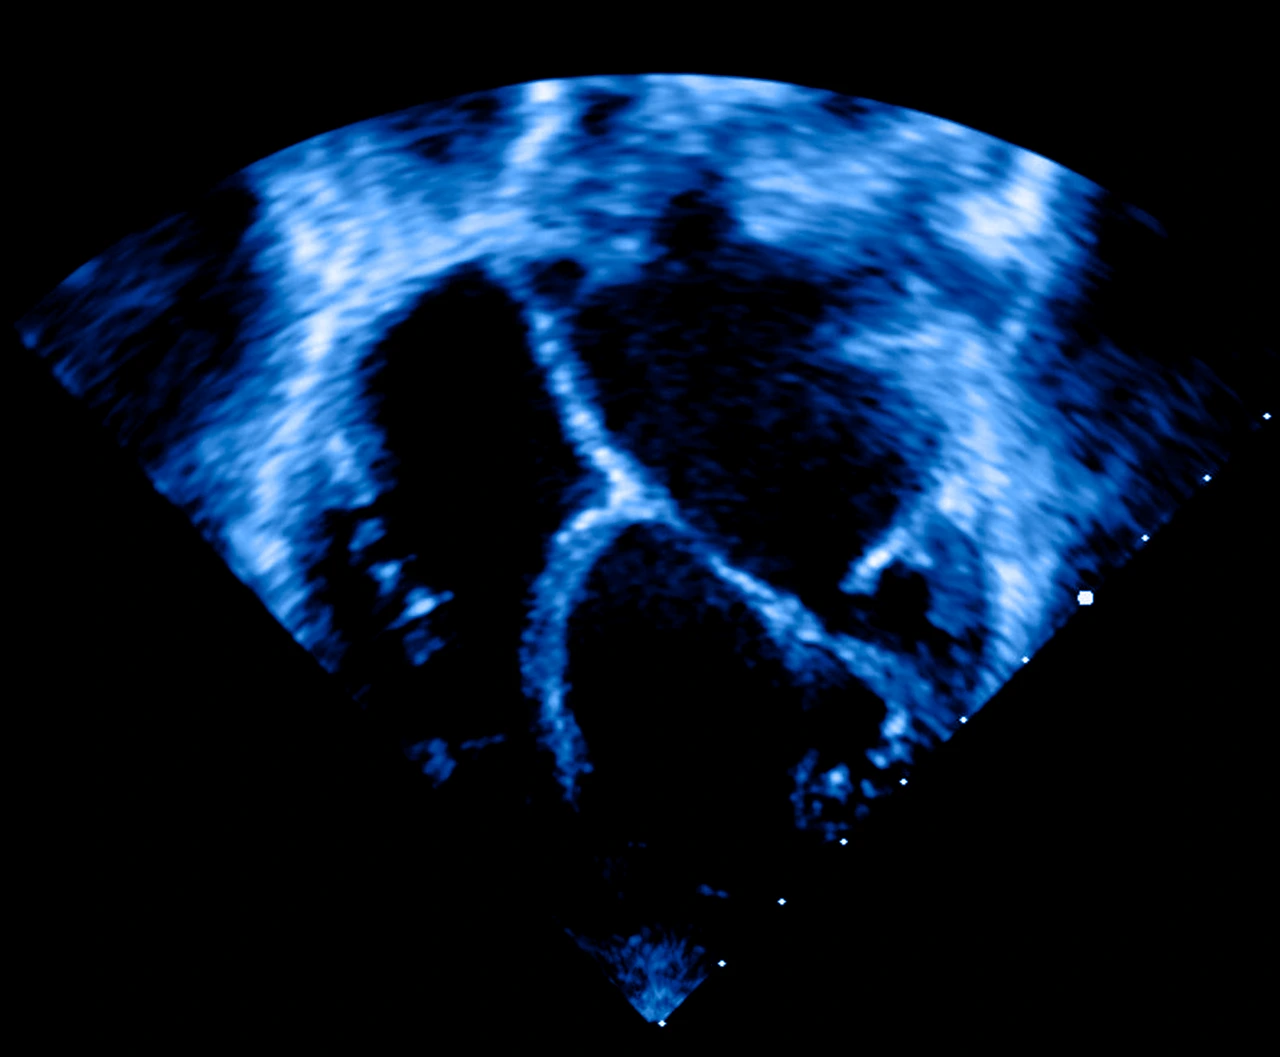

• El ecocardiograma es un estudio de imagen clave para evaluar el tamaño y la función de los ventrículos.

Ecocardiograma bidimensional de paciente con cardiomiopatía dilatada, donde se ve cómo está el corazón agrandado.

Existen también otros estudios más específicos, como el cateterismo cardíaco, la resonancia magnética o la tomografía computarizada, que permiten estudiar la estructura y el flujo sanguíneo del corazón con mayor detalle.